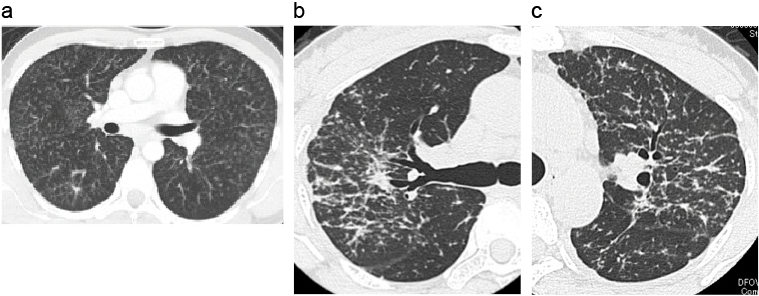

サルコイドーシスの両側肺門リンパ節腫脹(BHL)

両側縦隔・リンパ節腫脹(BHL)を発見された54歳の女性。典型的な両側肺門リンパ節腫大で、BHLは健康診断などで偶然発見されることが多い。そのような場合は無症状のことが多く、無治療で自然経過を観察する。